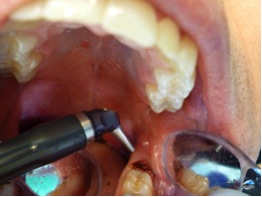

Fig 8. The angled handpiece of the CO<sub>2</sub> laser was held perpendicular to the target lesion.

Figure 8

Fig 9. The ablation of the inflamed tissue began.

Figure 9

2. The angled handpiece of the CO2 laser was held perpendicular to the target lesion (Figure 8) and the ablation of the inflamed tissue began (Figure 9). The dental surgeon was careful to avoid contact between the laser beam and the tooth enamel. (Note: In this case, the inflamed tissue was located distally from the involved molar. There was no direct contact of the beam with the tooth, as the surgeon was careful not to hit the enamel. However, if an operculum covers part of the tooth, an adaptive tool (for example, a wax spatula) needs to be inserted between the tissue and the tooth to prevent possible damage. For an inexperienced CO2 laser surgeon, it is important and highly recommended to always shield the tooth during the procedure.6)